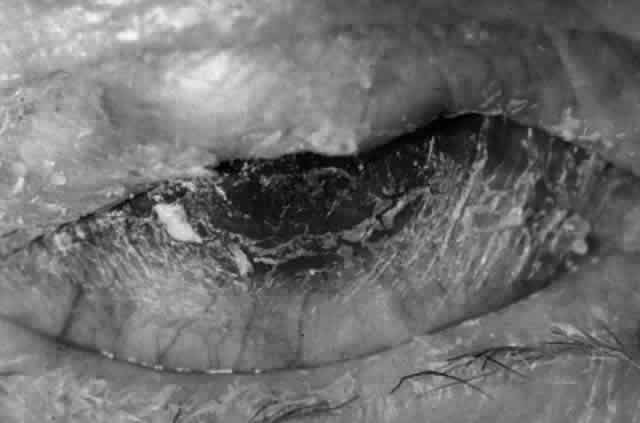

Cicatricial pemphigoid (CP) is a chronic cicatrizing autoimmune disease of the mucous membranes and skin. It is said to have an average age of onset of 65 years, but this figure under-reports the true epidemiologic features of this disease, because the cases are usually not in their earliest stages.17 Females are affected two to three times as frequently as males. Conjunctival involvement may occur as early as 10 years before other mucosal or skin lesions develop, or it may occur as late as 20 years after the onset of other lesions; the disease may be limited to the conjunctiva (Fig. 5). The scarring Brusting-Perry dermatitis occurs in approximately 25% of cases (Fig. 6), and cicatrizing conjunctivitis develops in 70% to 75%.17,18 Involvement of other mucosa may lead to scarring of the soft palate and oral and nasal mucosa, and esophageal, urethral, vaginal, and anal strictures may develop. Laryngeal involvement may cause pain and hoarseness,19 and the esophageal scarring can be lethal, because asphyxiation can result from a food bolus that is lodged during attempted swallowing by a patient with dysphagia from esophageal strictures that have been neglected by patient and physician alike.

Fig. 5. Eye of a patient with cicatricial pemphigoid, biopsy-proven, without extraocular manifestations. The disease has progressed to end stage and blindness. Note the total “leatherization” of the eye, with complete adherence of the eyelids to the globe.